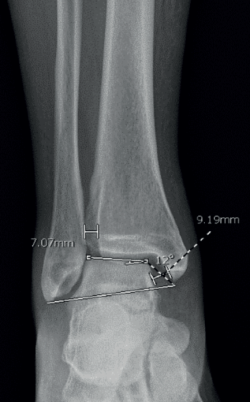

Realizamos las siguientes mediciones radiológicas en la proyección de mortaja del tobillo (rotación interna de 20°) antes de la cirugía, en el tobillo afectado y en el sano, y al final del seguimiento (Figura 3):

- Espacio claro medial (ECM).

- Espacio claro tibiofibular (ECTF).

- Ángulo cruromaleolar (ACM).

Todas las mediciones fueron llevadas a cabo por un único examinador, el becario del equipo, entrenado en cirugía de tobillo y pie. Se utilizó un programa computarizado (Synapse® Picture Archiving and Communication System). Todas las imágenes fueron digitales. Se midió el ECM y el ECTF en mm y el ACM en grados, siendo sus valores normales(19):

- ECM ≤ 4 mm.

- ECTF < 6 mm.

- ACM = 12 a 14°.

Se registró el promedio en mm de la medición del ECM y el ECTF, y en grados del ACM, en el tobillo sano y en el tobillo fracturado antes de la cirugía y al final del seguimiento.

Figura 3. Medición preoperatoria del espacio claro medial (9,19 mm), el espacio claro tibiofibular (7,07 mm) y el ángulo cruromaleolar (12°).